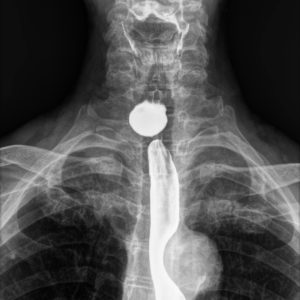

Túi thừa thực quản